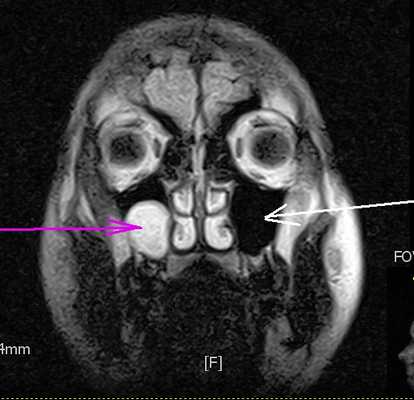

При КТ видна характерная кальцификация по краям кисты. При МРТ головного мозга киста представляет собой мелкие четко очерченные ликворные образования. Дифференциальную диагностику при МРТ головного мозга надо проводить с :